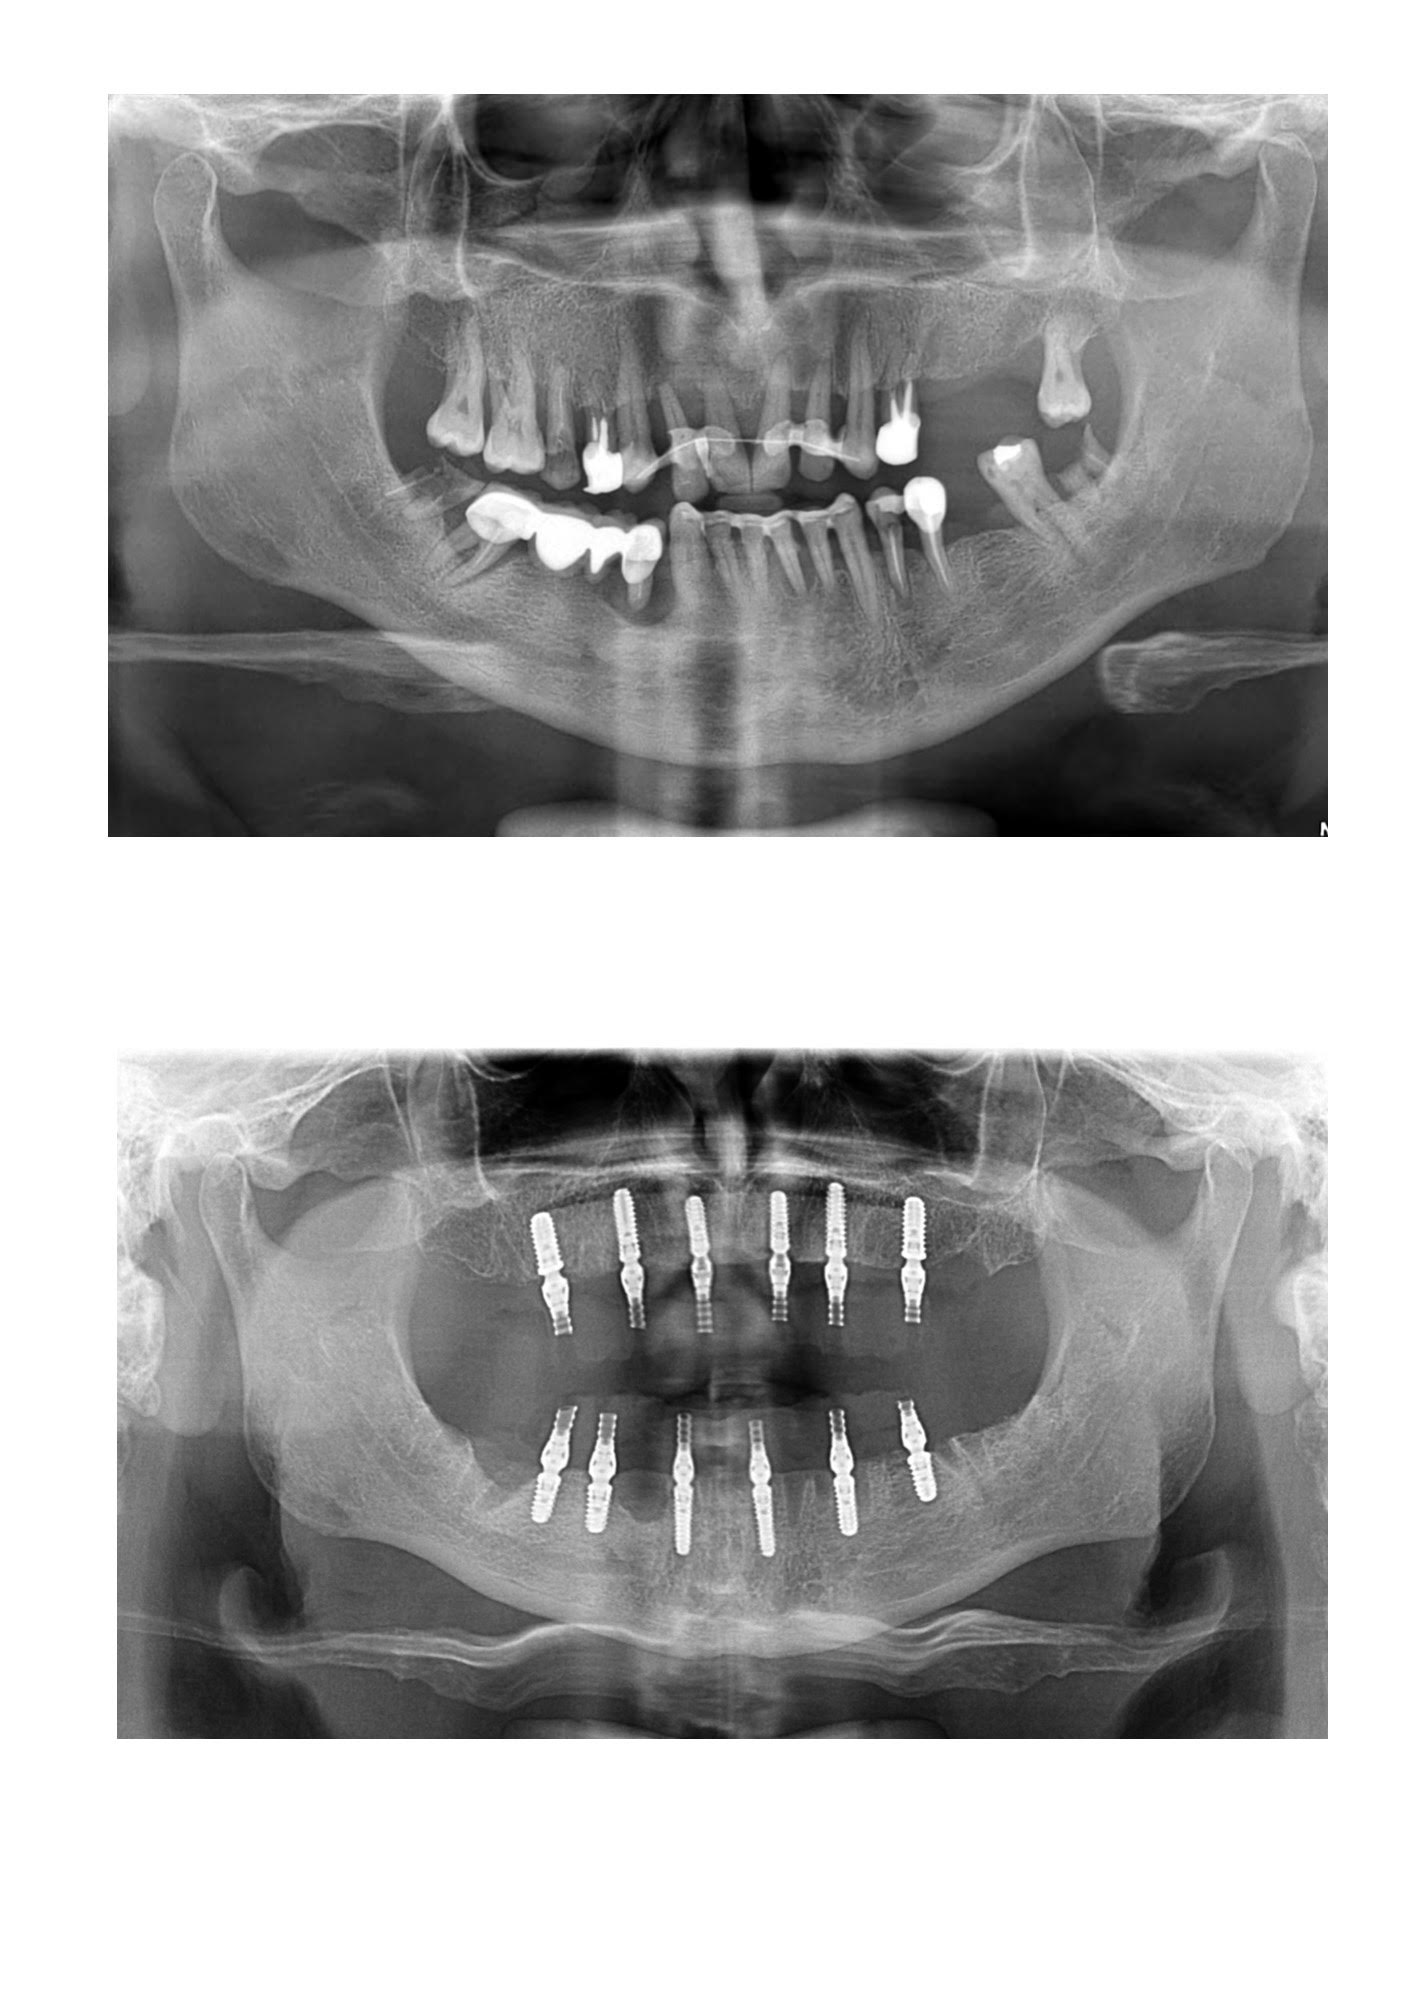

Domnul M. a venit la clinica DentOP cu o boală parodontală agresivă netratată de mult timp. Deși avea mulți dinți pe arcadă, aceștia au fost extrași pentru că nu ajutau. S-au făcut extracții atât sus cât și jos pentru a elimina dinții și gingiile afectate.

În cadrul aceleiași ședințe, domnului B. i-au fost inserate 12 implanturi, iar în doar 24 de ore și-a recăpătat zâmbetul și masticația cu ajutorul lucrărilor provizorii.

În pozele de mai jos putem observa rezultatul său.